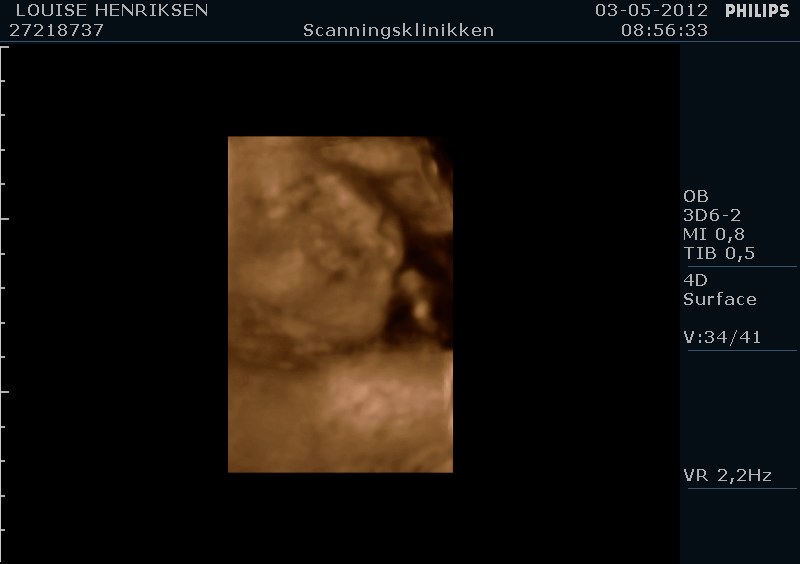

I dag skulle manden overraskes med en 4 d scanning.... og hans far var også med det var også en overraskelse, samt den lille prins....han fik bind for øjene og vi kørte mod scanning klinikken.... vi fik nogle gode sekvenser af bettemanden.. men han fylder en del derinde nu, så billederne blev ikke voldsomt gode.. men nogle fik vi dag...jeg skulle i morgen være 32 fulde uger.. mne scanningen i dag vidste34+4 dage yiarks.... jeg skal til at være færdig med den bachelor..... han vejede efter målene 1871 gram.....

så han var en fin basse...

Sikke nogle fine billeder

Men det er da en lille vægt hvis du sku være så langt? Min lillefis blev skønnet til 2300 g da jeg var 34+0, og det sagde jm var lige på gennemsnittet.. Mon ikke der kan være sket en tastefejl hos scanningen?

Men det er godt nok en fin lille basse.. Åh det er så hyggeligt med scanninger --> savner det!